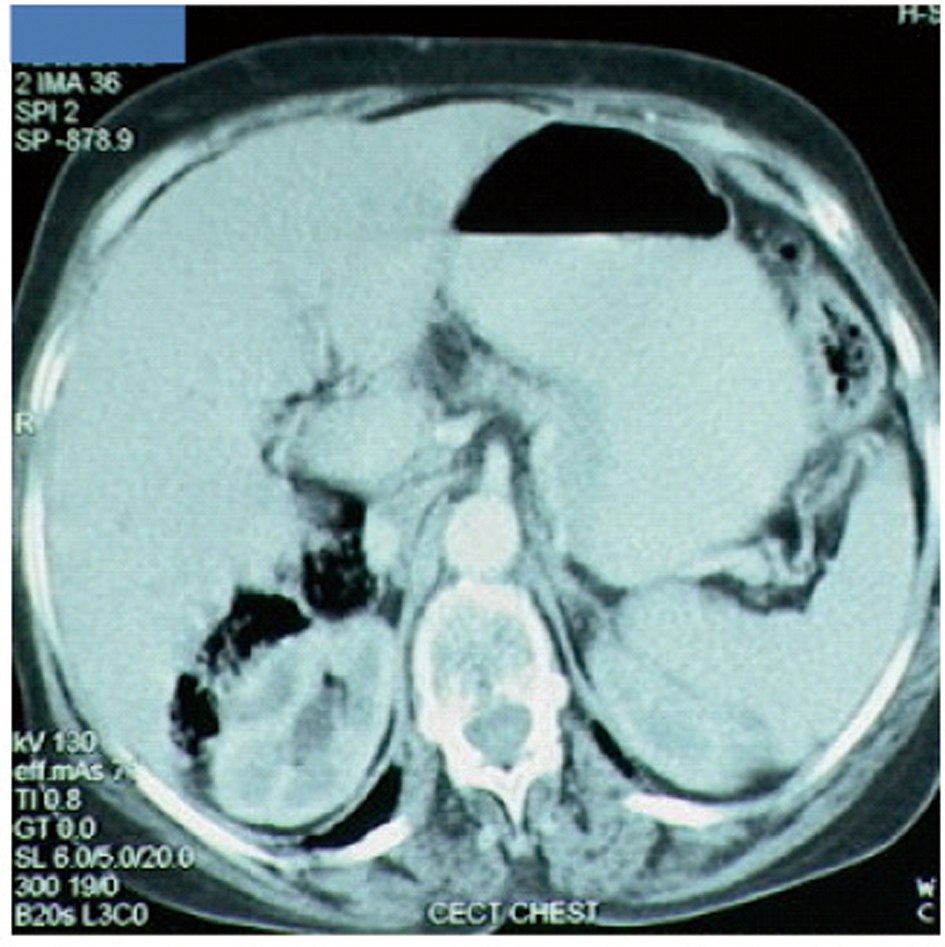

A 65-year-old postmenopausal woman presented in May 2007 with vomiting, early satiety and 20 lbs weight loss over last 2 months. There was no history of associated fever, cough, bleeding from any site, and the family history was also insignificant. On examination, pallor was present. However, no icterus, edema or lymphadenopathy was noted. Detailed systemic examination revealed no abnormality. Investigations revealed mild anemia (Hb 9.8 g/dL) and elevated alkaline phosphatase levels (310 U/L). Esophagogastroduodenoscopy (EGD) showed large ulcerated lesion at the fundus, extending into the esophagus. CECT abdomen showed mass lesion in gastric cardia extending to involve the gastroesophageal junction and fundus, with compression of fat planes and wall thickness of 44 mm. There were multiple space occupying lesions (SOLs) in the right lobe of liver, the largest measuring 4.3 x 3.1 cm (Fig. 1). Tissue specimens from endoscopic biopsy (gastric region) and CT guided FNAC of liver showed moderately differentiated adenocarcinoma. Hence, a diagnosis of gastric carcinoma with liver metastases was made. Tumor markers - CEA and CA 72.4 levels were 1.7ng/mL and 0.99 U/mL respectively. The patient was then started on chemotherapy regimen consisting of docetaxel, oxaliplatin and capecitabine (DOX). Docetaxel was administered as 25 mg/m2 followed by oxaliplatin 50 mg/m2 on days 1 and 8, with capecitabine 625 mg/m2 BID from days 1 to 14, in 21-day cycles. The protocol was well tolerated by the patient except for grade 2 hematologic toxicity, which responded to blood product transfusions, erythropoietin and G-CSF. Patient also experienced diarrhea, managed with supportive therapy. A thorough workup done was after 3 and 6 cycles of chemotherapy to evaluate the response. Investigations at the end of 6 cycles of chemotherapy (November 2007) showed decreased gastric lesion, with a wall thickness of 8 mm on CT abdomen (Fig. 2); the particular liver lesion also decreased in size to 1.3 x 1.1 cm. EGD revealed few small erosions in fundus near the gastroesophageal junction, no ulcer or growth was seen. CT abdomen done 3 months later (February 2008) showed complete absence of gastric and liver lesions (Fig. 3). This patient responded dramatically to the chemotherapy protocol, as evidenced by > 50% decrease in the size of gastric and liver lesions after 6 cycles of chemotherapy, and complete disappearance of the lesions after further 3 months. Hence the patient’s clinical response to chemotherapy was labeled as CR. The patient continued to maintain CR for about 9 months, since the initial response.

![]() Click for large image | Figure 3. Disease status at 9 months after diagnosis. Complete disappearance of gastric and liver lesions. |